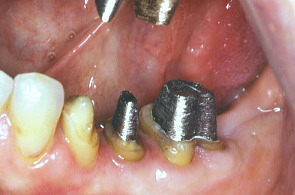

歯冠がないところにはポスト(芯)を入れる。左がプラスチック、右はそれを鋳型にして金属にしたもの。